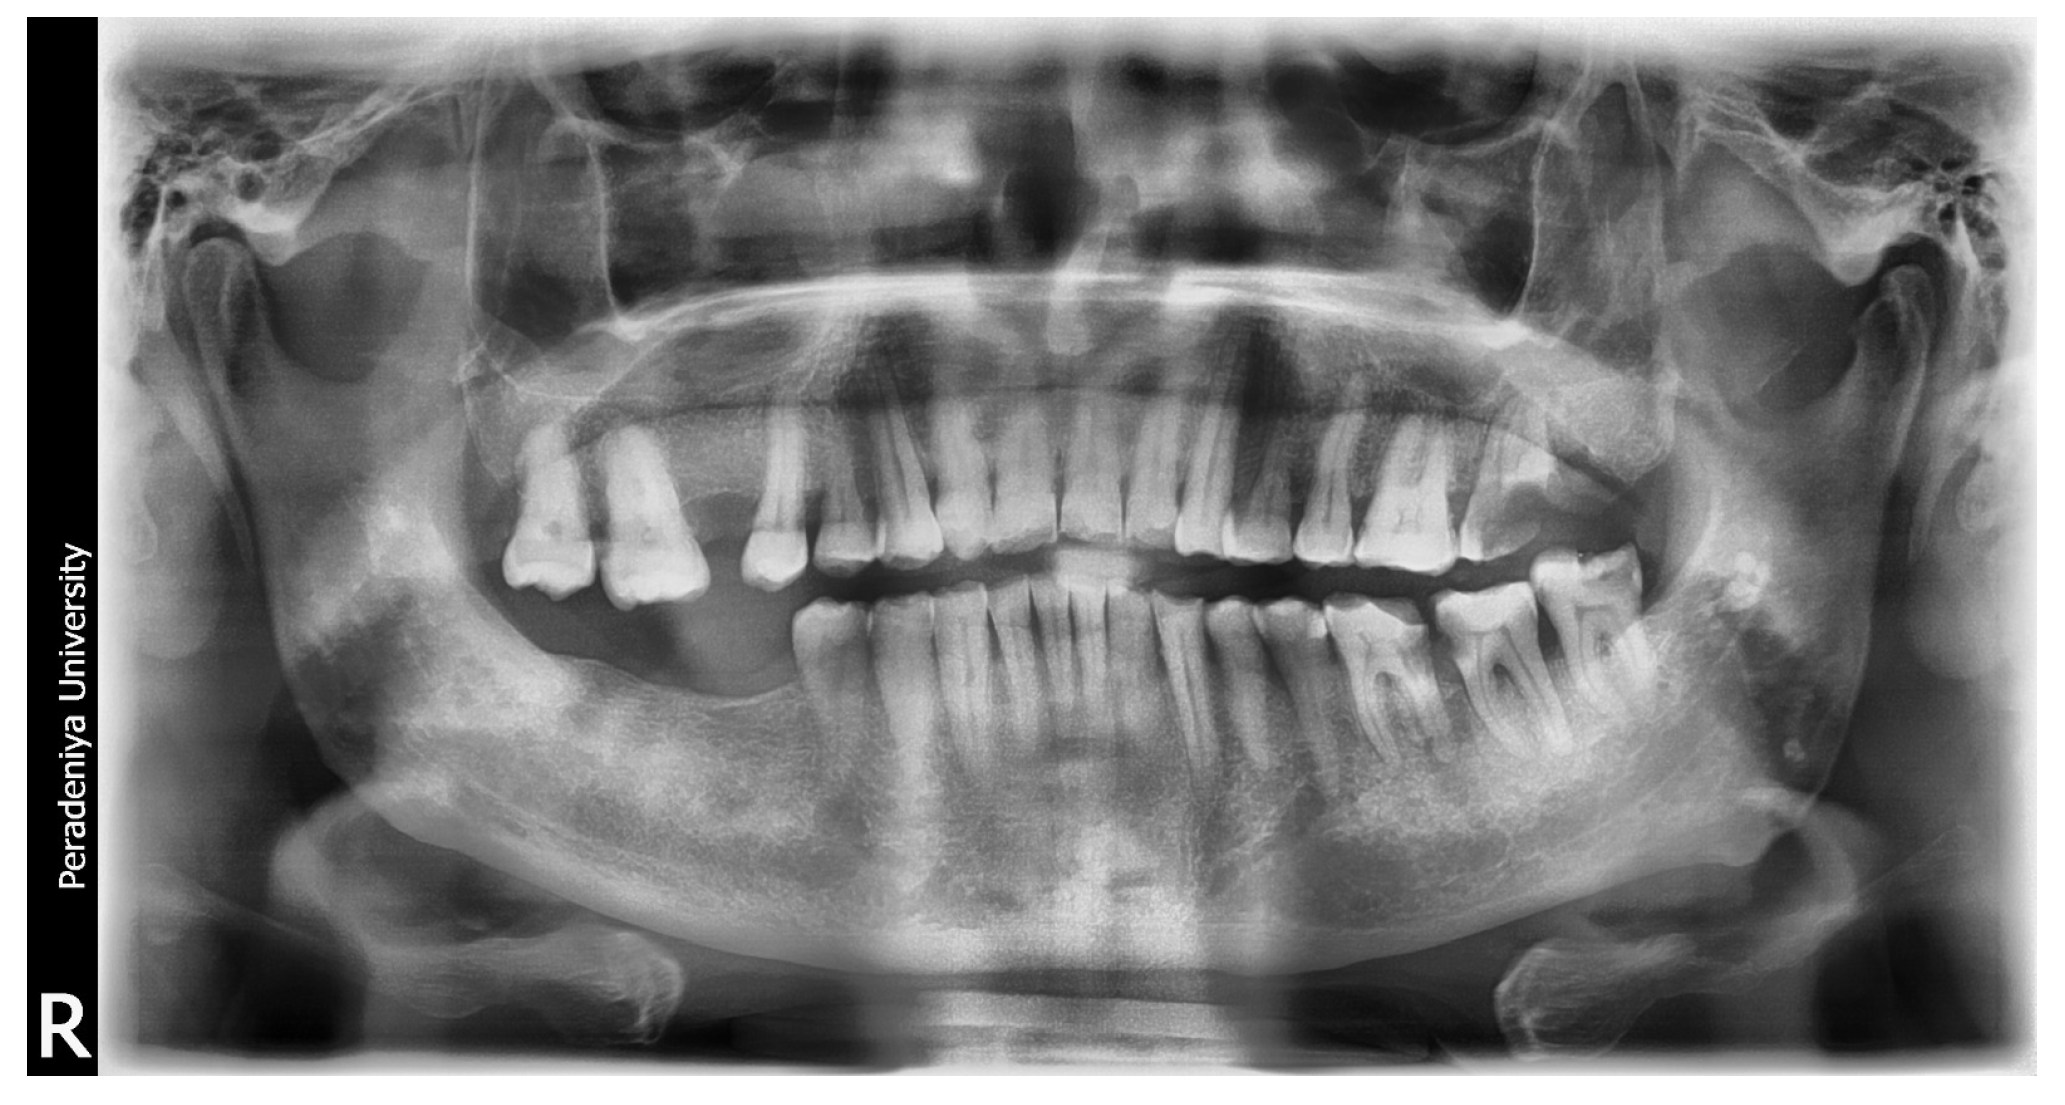

One of the four datasets, named The DPT Image and Caption Dataset, comprises 1000 image–caption pairs of DPT images. Each image in the dataset was descriptively annotated by a panel of experts specializing in dental and maxillofacial radiology, each with over 10 years of experience. These annotations provide detailed and clinically relevant captions for each image. Figure 1 shows the distribution of oral complexities in the DPT image dataset. The disparity in the frequency of occurrence of each oral complexity in the general population causes the class imbalance in this dataset. Adhering to the ethical committee suggestions, a subset of this dataset has been made available publicly under the Apache License 2.0, allowing for its utilization in future research within the domain. This dataset can be accessed using [31]. Table 1 shows samples of the DPT Image and Caption Dataset [31], i.e., image–caption pairs.

Figure 1.

Case distribution for the DPT image dataset.

4.2. Radiology Report Generation: Blip-2 Results

The performance of the fine-tuned Blip-2 model was evaluated, both qualitatively and quantitatively, on 100 DPT image–caption pairs. The evaluation focused on the accuracy of the captions generated for the corresponding DPT images. Figure 8 illustrates the total number of cases against the correctly identified cases for each dental condition detected in DPT images. It should be noted that some DPT images indicate more than one dental condition, hence, there are more cases than the number of DPT images in the test set.

Figure 8.

Total number of cases and correctly identified cases for the test set.

The findings indicate that the model can accurately identify 87.9% of dental caries, 89.7% of impacted teeth, 88% of bone loss, and 81.8% of periapical lesions. These four cases were the dental conditions that produced a detection accuracy above 80%. Bone fractures and orthodontic issues had the lowest detection accuracy, with 60% and 62.5% accuracy values, respectively. The decreased number of cases in the training dataset is the primary cause of the lower ratings for these two conditions. Therefore, model performance can be enhanced over time by increasing the size of the dataset and the density of cases for each dental condition.